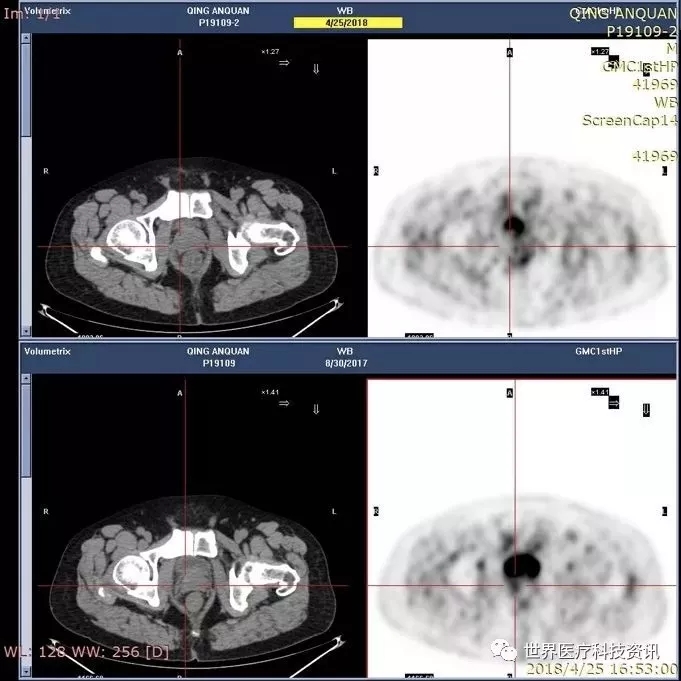

而是治疗结束之后,肿瘤才缩小,我们不敢相信这个病人的复查结果,就请他回广州做一个更先进的检查叫做PET、CT ,这个结果一看,合格病人的病灶的代谢活性消失了。

用老百姓的话来说,病人的肿瘤死了,只留下一个疤痕,上面的那个图,交叉线的那个代谢活性是没有了。所以这个病人到现在一年半,没有任何的临床症状。